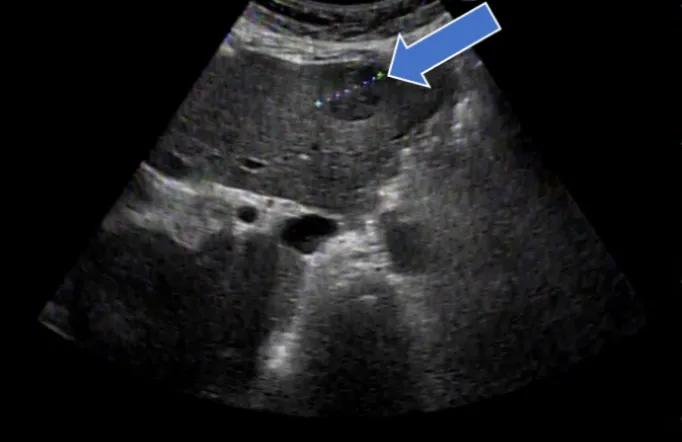

肝がんの検査には、血液検査と超音波(エコー)検査(写真2)、CT検査(写真3)、MRI検査といった画像検査を組み合わせて行います。CT検査やMRI検査では造影剤を使用して詳細な検査を行いますが、腎機能低下や透析症例でも安全に使用できる「造影剤」を用いて行う造影エコー検査(写真4)も週1回外来で行っています。

• (写真2)肝がんのエコー写真